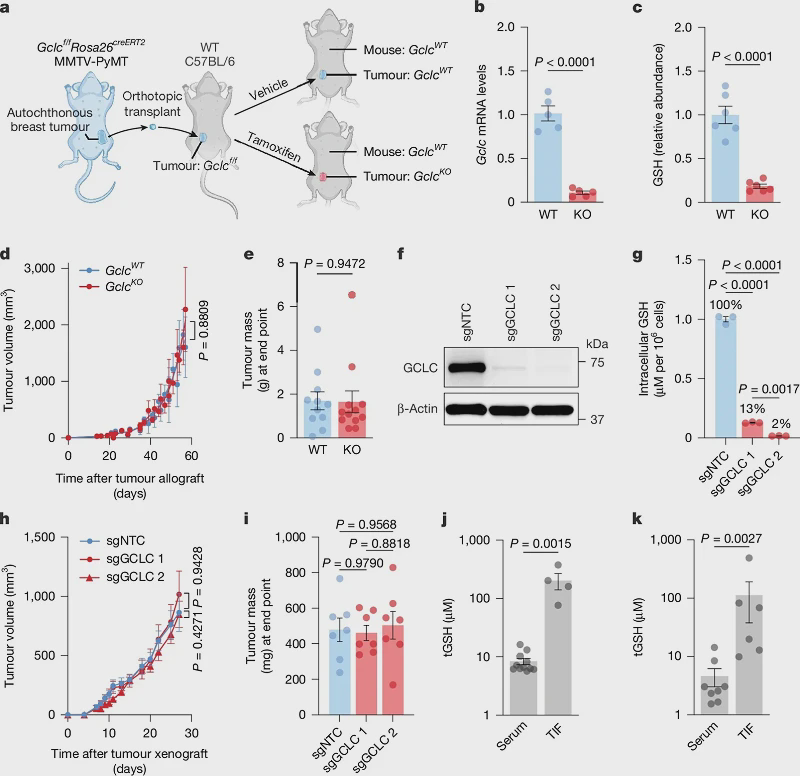

Glutathione is even more powerful! Latest research shows: Without it, immune cells become paralyzed and tumor metastasis becomes uncontrollable!

Amino acids are crucial in the initiation, progression and resistance of tumors. The limited supply of amino acids in the tumor microenvironment restricts their acquisition, and this has become a promising anti-tumor strategy. Cysteine has